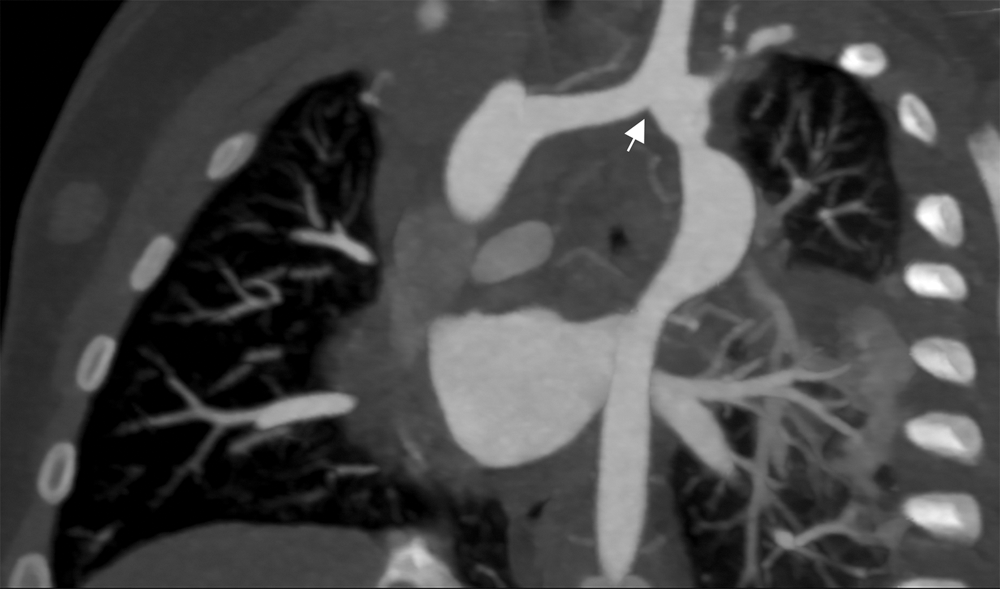

Cardiac CT (Figs. 2–4) identified an ascending aorta that gave rise to dilated common carotid arteries and an extremely tortuous and stenotic right aortic arch. The right subclavian artery originated beyond the area of severe arch stenosis with an additional area of narrowing at its origin. Collateral vessels were seen in the right side of the neck. A long and relatively narrow right-sided dorsal aortic root passed in a caudal direction where it was joined by an equally long but larger left-sided dorsal aortic root reflecting ductal flow in utero. The dorsal roots fused below the level of the carina. The descending aorta was also right-sided but crossed to the left at the level of the diaphragm. The left-sided dorsal root remnant supplied an aberrant left subclavian artery, a dilated left vertebral artery, and collateral vessels in the left side of the neck. There was no evidence of a double aortic arch.

Figure 3: A coronal 3D reconstruction viewed from posterior, shows stenosis of the right sided arch (large arrow), and stenosis of the proximal right subclavian artery (small arrow). The dorsal aortic roots are long and the left sided dorsal root is larger than the right indicating ductal flow in utero